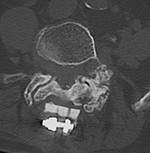

| 85 year-old woman. These images show respectively an AP radiograph of an ILIF at L4-5, an axial CT image of the ILIF, and two coronal reformatted CT images of the ILIF. There is a donar bone plug held in place by the interspinous fixation plate (clamp). |